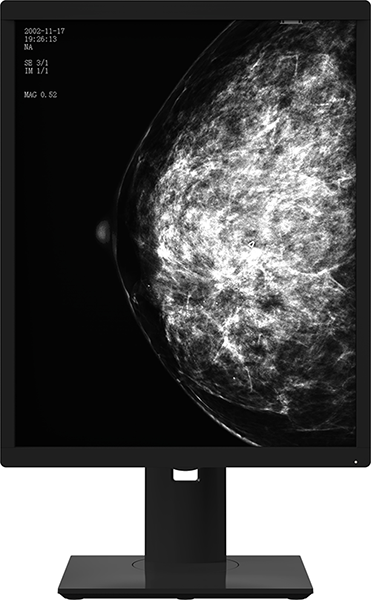

La pantalla médica en escala de grises de 5 megapíxeles de la serie 21X5M cuenta con un rendimiento excepcional y está diseñada específicamente para entornos médicos. Su impresionante resolución en escala de grises, su procesamiento monocromo y su alto rendimiento garantizan una calidad de imagen exacta y precisa. Esta pantalla es la herramienta definitiva para los médicos, ya que les proporciona una base de diagnóstico estable y fiable que es a la vez clara y precisa.

Al utilizar un diseño libre y proporcionar un amplio espacio visual, esta herramienta ayuda a los médicos a lograr el diagnóstico clínico y el tratamiento más precisos para sus pacientes. Permite la visualización simultánea de varias imágenes de examen, incluidas tomografías computarizadas y resonancias magnéticas en un formato de mosaico, lo que facilita la comparación. Esta función también permite al personal médico ver y comparar imágenes de escaneo nuevas y antiguas simultáneamente, lo que mejora en gran medida su eficiencia diagnóstica. El producto se utiliza principalmente junto con máquinas mamarias digitales, y las imágenes de rayos X resultantes se presentan a reconocidos profesionales médicos como la base para la detección o el diagnóstico del cáncer de mama.